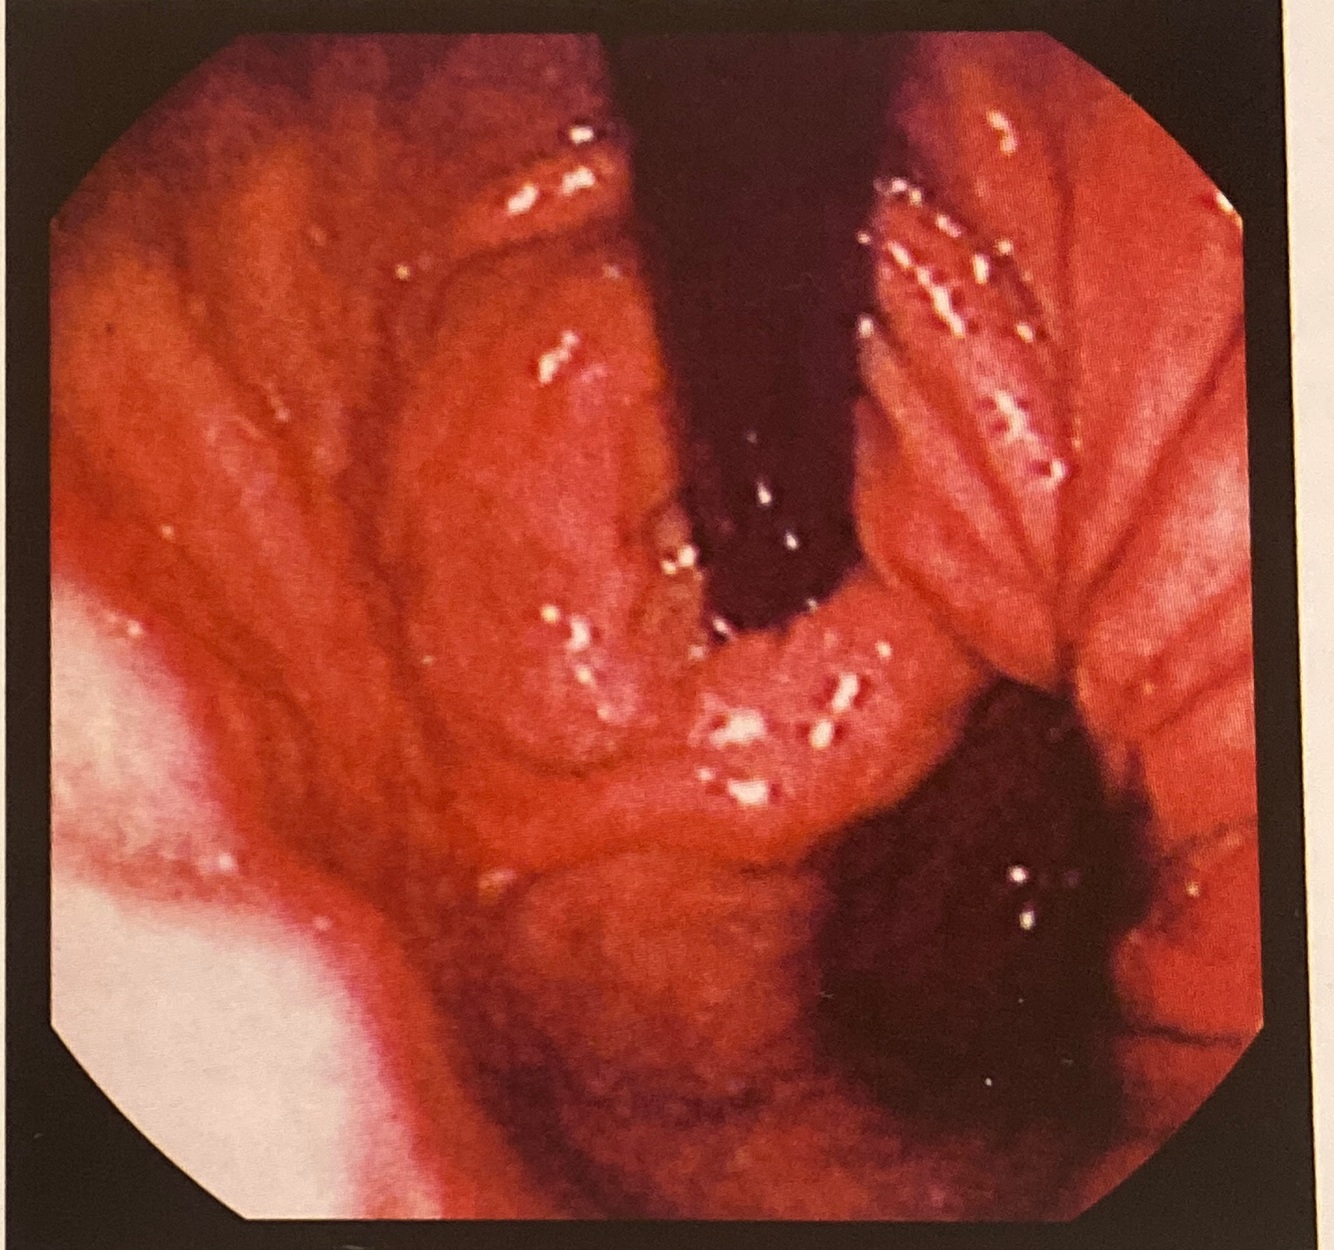

Esôfago típico de

Esofagite herpetica: múltiplas úlceras superficiais